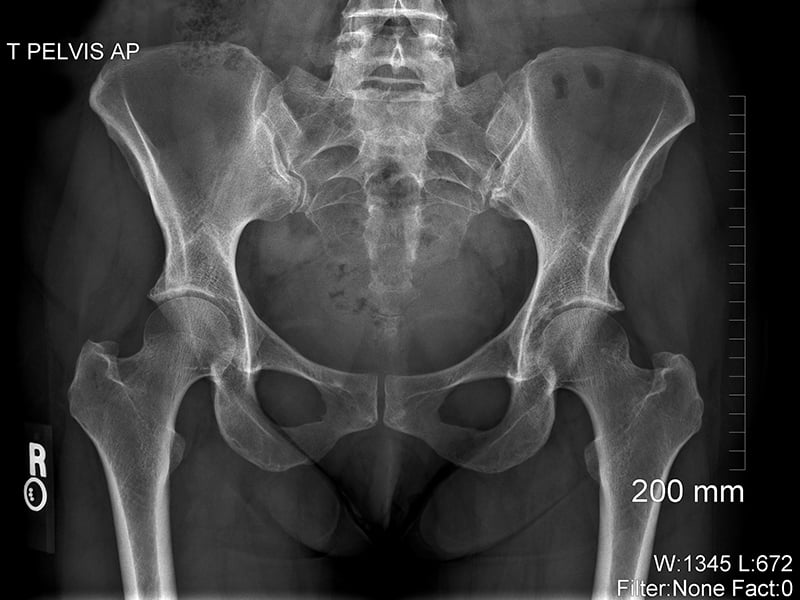

X-rays are a type of radiation. They’re an energy source similar to light, but they have a much shorter wavelength and can pass through the human body. As x-rays pass through the body, some energy particles called photons are absorbed, and some pass all the way through. The parts of the body made up of dense material, such as bone, show up as white areas on an x-ray image (the image itself is called a ​radiograph). The less dense parts, like the lungs, show up as darker areas.

X-ray of pelvic

X-ray